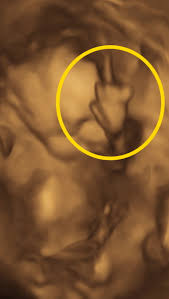

• ways to turn breech baby

• turning breech baby spinning babies

• flipping babies breech

• why do babies go breech

• baby turning around

• positions to flip breech baby